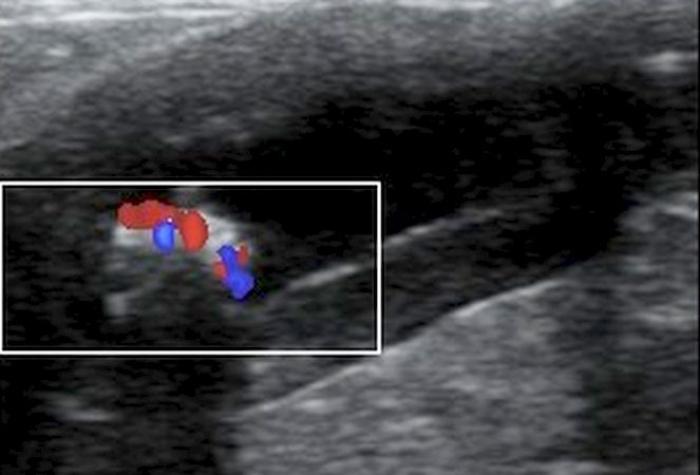

El estudio ultrasonográfico abdominal se realizó con un ecógrafo marca Mindray® modelo Z60Vet®, con transductor de 12 MHz. El estudio reveló los siguientes hallazgos (Figura 2-4):

- Hiperecogenicidad difusa e irregularidad de contornos en la rama derecha del páncreas.

- Dilatación del conducto pancreático derecho, alcanzando 0.49 cm de diámetro.

- Imagen hiperecogénica intraductal con sombra acústica posterior y artefacto de centelleo en Doppler color, compatible con litiasis.

El hallazgo ecográfico de estructuras hiperecogénicas intraductales con sombra acústica posterior, asociado a la dilatación del conducto pancreático, fue fundamental para la sospecha diagnóstica de litiasis pancreática. Esta combinación ha sido descrita previamente como una de las principales herramientas de diagnóstico por imagen en casos de pancreatolitiasis felina9,10. El uso de Doppler color, que permite identificar artefactos de centelleo o twinkling, ha demostrado aumentar la sensibilidad para detectar minerales intraductales como el carbonato de calcio11.